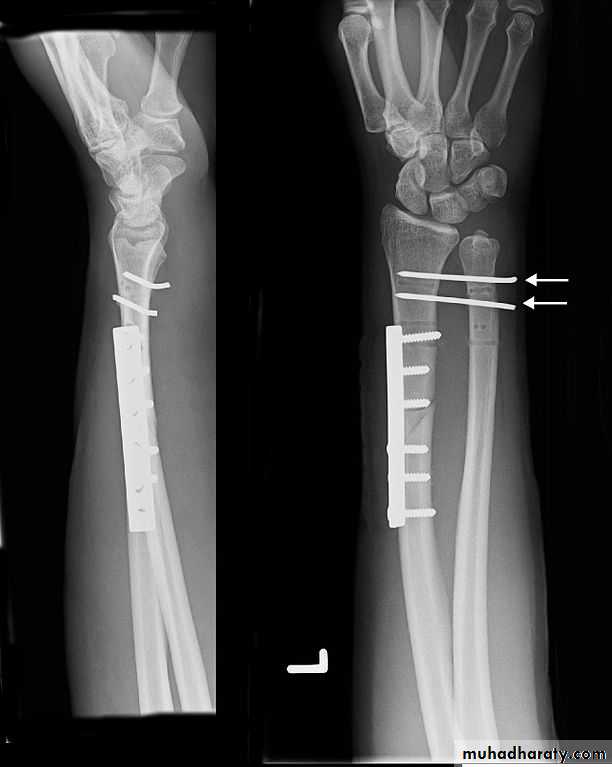

Upper limb

Fall on out stretched hand

xray